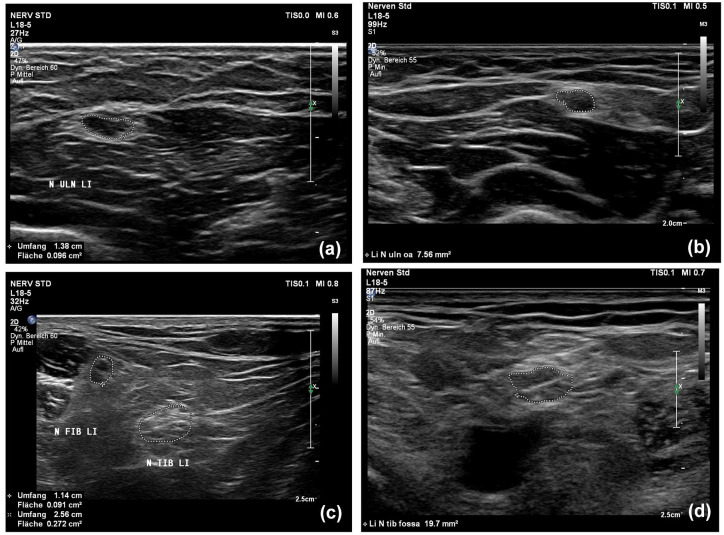

Methods and design: We longitudinally examined 12 CIDP patients from 2016 to 2022 using NUS, MRN, nerve conduction studies (NCS), and clinical parameters (inflammatory neuropathy cause and treatment (INCAT)/overall disability sum score (ODSS)). NUS evaluated the cross-sectional area (CSA) of the median, ulnar, radial, tibial, fibular, and sural nerve as well as the intranerve CSA variability (INVcsa) of the tibial, fibular, ulnar, and median nerve, whereas MRN evaluated T2-weighted sequences of the fibular and tibial nerve at the popliteal fossa.

Results: Five patients showed clinical improvement/stability with corresponding improved or stable NCS/NUS parameters (number of nerves with increased CSA and INVCSA). Seven deteriorating patients showed deteriorating NCS and either increasing or decreasing NUS markers possibly indicating inflammatory activity or degenerative CSA reduction. The difference ΔINCAT/ODSS2022-2016 correlated positively with NUS ΔINVCSA2022-2016 (p = 0.007, r = 0.731, n = 12) and with NUS ΔCSA2022-2016 of the tibial nerve (p = 0.0005, r = 0.865, n = 12). Further, NUS-CSA of the tibial nerve in the popliteal fossa in 2016 correlated inversely with the difference of the INCAT/ODSS score (ΔINCAT/ODSS2022-2016; r = -0.653; p = 0.033; n = 11). Finally, the Bland-Altman analyses for the tibial and fibular nerve showed a bias of -1.903 and 2.195 mm2 (bias = NUS-CSA - MRN-CSA) accordingly revealing a difference between MRN and NUS measurements for deeper nerves.

Conclusion: CSA and INVCSA of the tibial and fibular nerve can be used for monitoring in CIDP, and increased CSA of the tibial nerve is a good prognostic marker. MRN is more reliable for evaluating inflammation in proximal leg nerve segments.